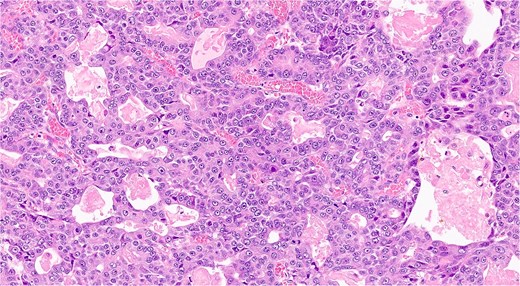

The analysis confirmed a well-differentiated acinar cell carcinoma with no lymphovascular or perineural invasion (Fig. 5). Resection margins were tumor-free. Examination of 13 resected lymph nodes showed no metastatic involvement. The tumor was staged as pT2 N0 M0 (Stage IB).

Histopathological slide showing well-differentiated acinar cell carcinoma with eosinophilic cytoplasm, monomorphic nuclei, and zymogen granules (hematoxilina-eosina staining, ×20 magnification).